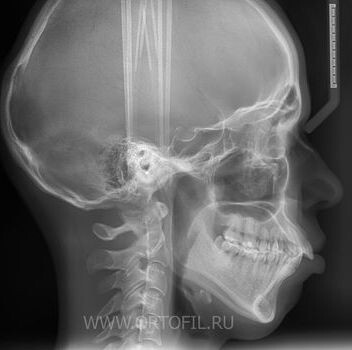

И если Вам не делали хотя бы боковую ТРГ... Да что делали... Если Вам внятно, на понятном русском языке, не рассказали резюме её анализа и не смогли четко обосновать приговор "удаление", не спешите соглашаться. Попробуйте получить альтернативное мнение.